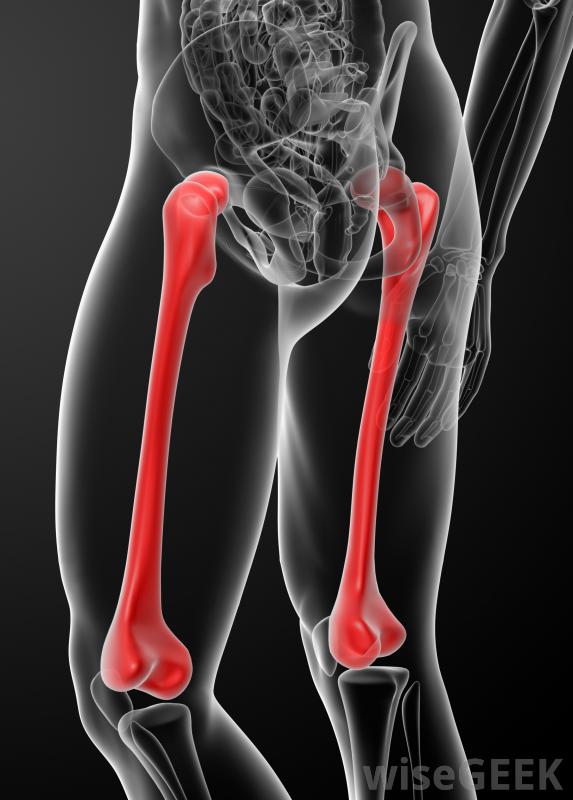

股骨頭內釘有兩種主要類型,順行和逆行。順行入路包括從股骨頂部或髖部插入股骨釘,而在逆行入路中,釘從膝蓋端進入。順行股骨釘是指治療股骨干骨折最常用的方法,而逆行入路有時可用于更復雜的骨折,如肥胖患者,或者是多處受傷的人。

老年人可能特別容易骨折。